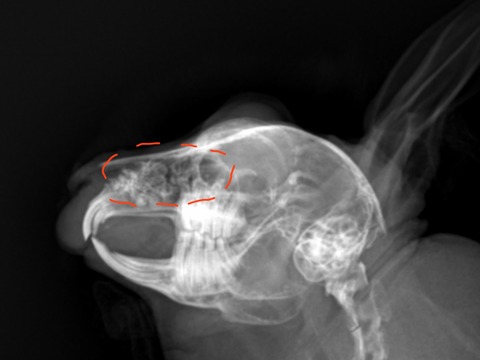

上顎臼歯(上側の奥歯)の歯根が不正なために炎症や感染を起こしてスナッフルの症状が出る時もあります

正常なうさぎの歯根と比べて揃っていない、ガタガタしているのがレントゲンで分かります

重症例や慢性経過の例では、レントゲンで歯根や鼻腔内の異常が無いかを調べます

骨変形を起こして鼻腔内が白くモヤっと見えることがあります